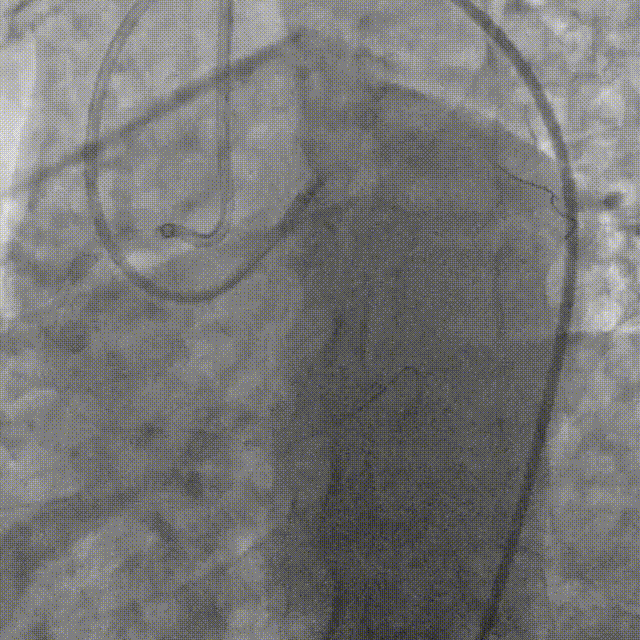

直接使用G3导丝rendezvous,球囊扩张后行IVUS检查确定血管直径及支架落脚点。

D1释放DCB,LAD植入支架后D1血流影响,工作导丝找回后使用球囊扩张并kissing。

造影发现LAD远端病变仍较重,释放DCB。

复查造影并行ivus检查 支架贴壁良好 无累及夹层。

RCA中段扩张后出现夹层,植入DES。